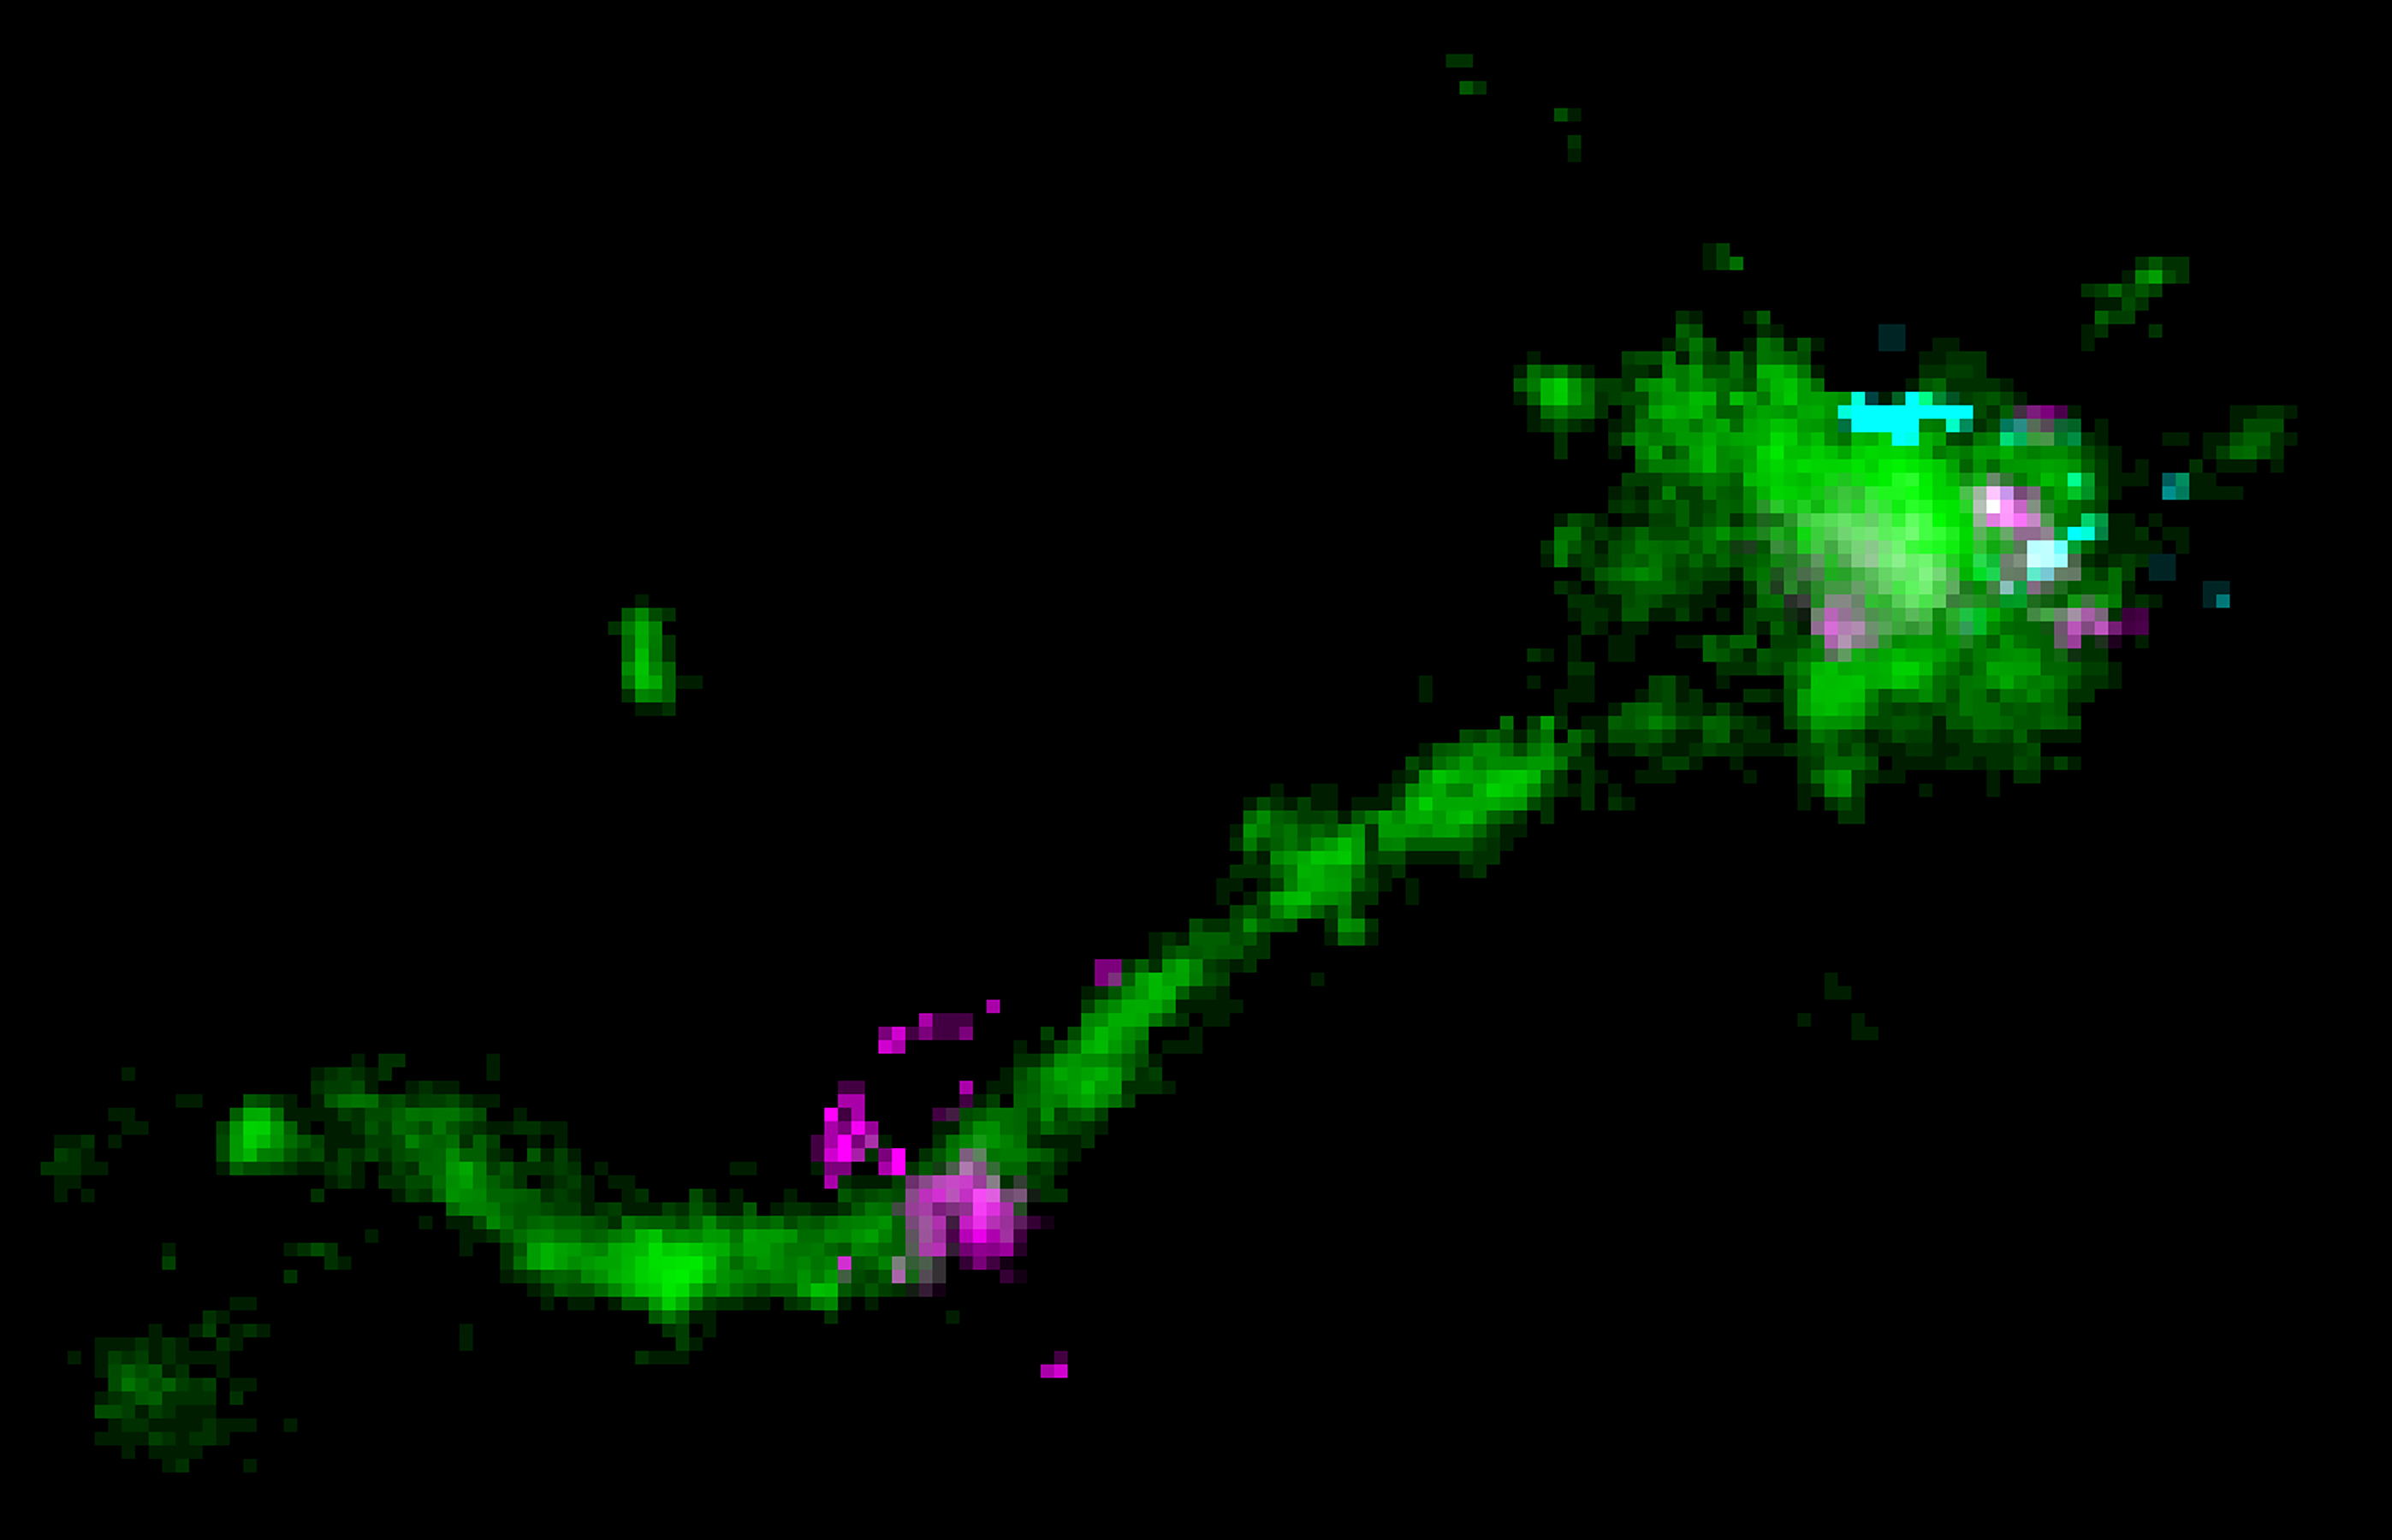

„Um in die Zelle zu gelangen, muss mRNA einen langen Weg zurücklegen. In den fettigen LNP-Tröpfchen eingeschlossen, muss sie zunächst erst einmal in die Zelle hinein“, erklärt Marino Zerial. „Die LNPs erreichen die Zelloberfläche, wo sie an Rezeptoren binden. Anschließend werden sie in Endosomen aufgenommen, spezielle Organellen, die von einer Membran umschlossen sind. Zu diesem Zeitpunkt befindet sich die mRNA innerhalb der Zelle, ist aber von zwei Barrieren umgeben: dem Fetttröpfchen und der Endosomen-Membran. Die Herausforderung für die mRNA besteht darin, beide Barrieren zu überwinden, um in das Zytoplasma zu gelangen, wo sie als Vorlage für die Herstellung von Proteinen dient. Wir wissen, dass nur ein winziger Bruchteil der mRNA-Moleküle in das Zytoplasma entweichen kann.“ Eingebrachte Frachtmoleküle, wie die LNPs, werden zunächst zu „frühen“ Endosomen transportiert. Dabei handelt es sich um zelluläre Logistikzentren, die die Frachtmoleküle an verschiedene Ziele in der Zelle verteilen. Sie recyceln die Moleküle entweder und bringen sie zur Zelloberfläche zurück oder bauen sie in späten Endosomen und Lysosomen ab. Bisher ging man davon aus, dass die mRNA aus den späten Endosomen entkommt, indem sie deren stark säurehaltigen Inhalt dazu nutzt, die Membran zu überwinden. „Mit Einzelmolekül-Mikroskopiertechniken“, erklärt Prasath Paramasivam, der Erstautor der Studie, „konnten wir zum ersten Mal die mRNA im LNP innerhalb der Endosomen der Zellen sichtbar machen. Wir konnten auch beobachten, wie die mRNA aus den röhrenförmigen der nur leicht sauren ‚frühen‘ Recycling-Endosomen entweicht.“ Zerial ergänzt: „Unsere Ergebnisse deuten darauf hin, dass die Weiterleitung der LNP-mRNA an späte Endosomen kontraproduktiv ist und die Zelltoxizität erhöht.“ Diese Ergebnisse ermöglichen es, den Mechanismus, mit dem mRNA aus den Endosomen entkommt, genauer zu verstehen.